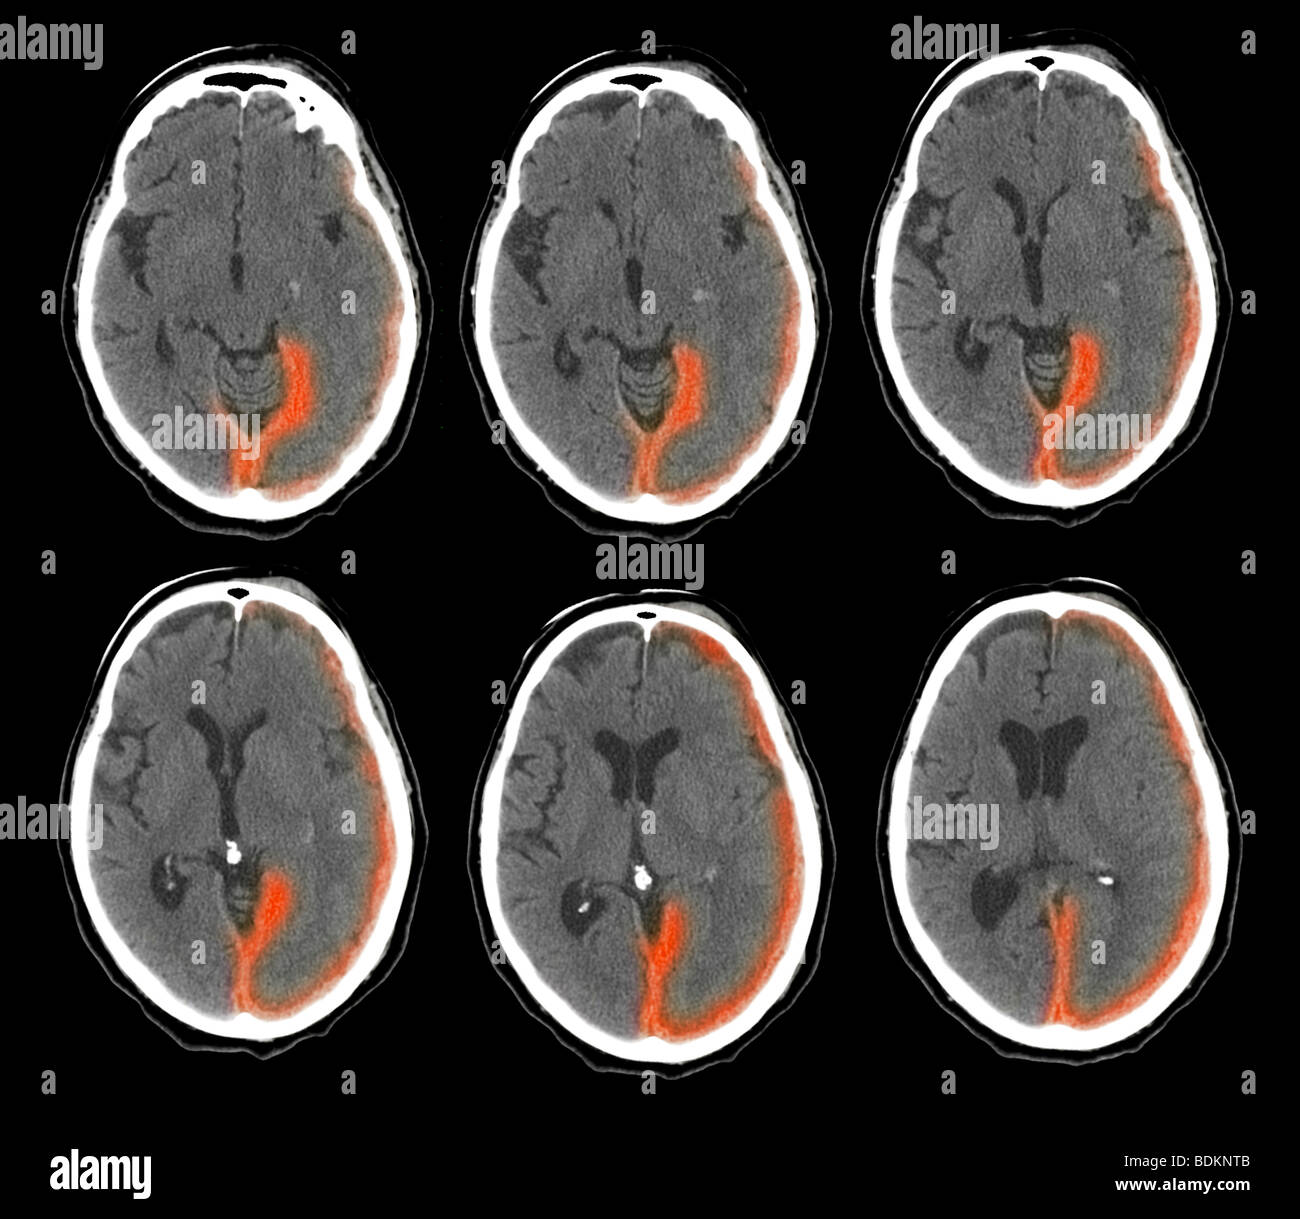

Scanographie du cerveau d'un homme de 73 ans montrent une hémorragie intracrânienne Banque D'Imageshttps://www.alamyimages.fr/image-license-details/?v=1https://www.alamyimages.fr/photo-image-scanographie-du-cerveau-d-un-homme-de-73-ans-montrent-une-hemorragie-intracranienne-25635131.html

Scanographie du cerveau d'un homme de 73 ans montrent une hémorragie intracrânienne Banque D'Imageshttps://www.alamyimages.fr/image-license-details/?v=1https://www.alamyimages.fr/photo-image-scanographie-du-cerveau-d-un-homme-de-73-ans-montrent-une-hemorragie-intracranienne-25635131.htmlRMBDKNTB–Scanographie du cerveau d'un homme de 73 ans montrent une hémorragie intracrânienne